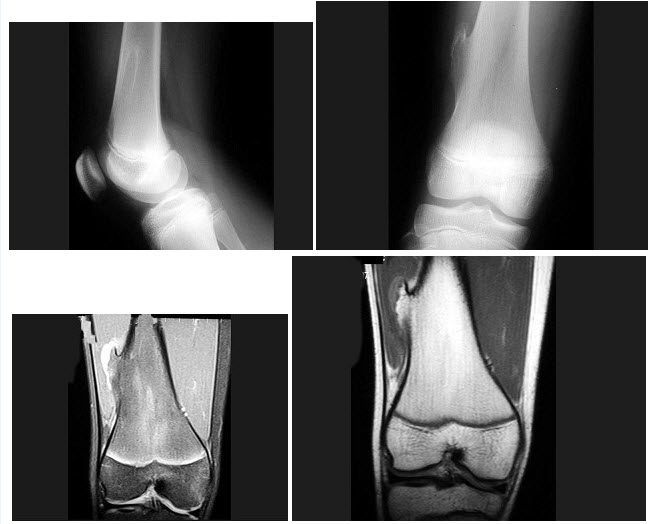

274、单项选择题

男,13岁,运动后膝关节疼痛,结合图像,最可能的诊断是()

A.正常影像

B.动脉瘤样骨囊肿

C.骨软骨瘤

D.成骨细胞瘤

E.骨样骨瘤